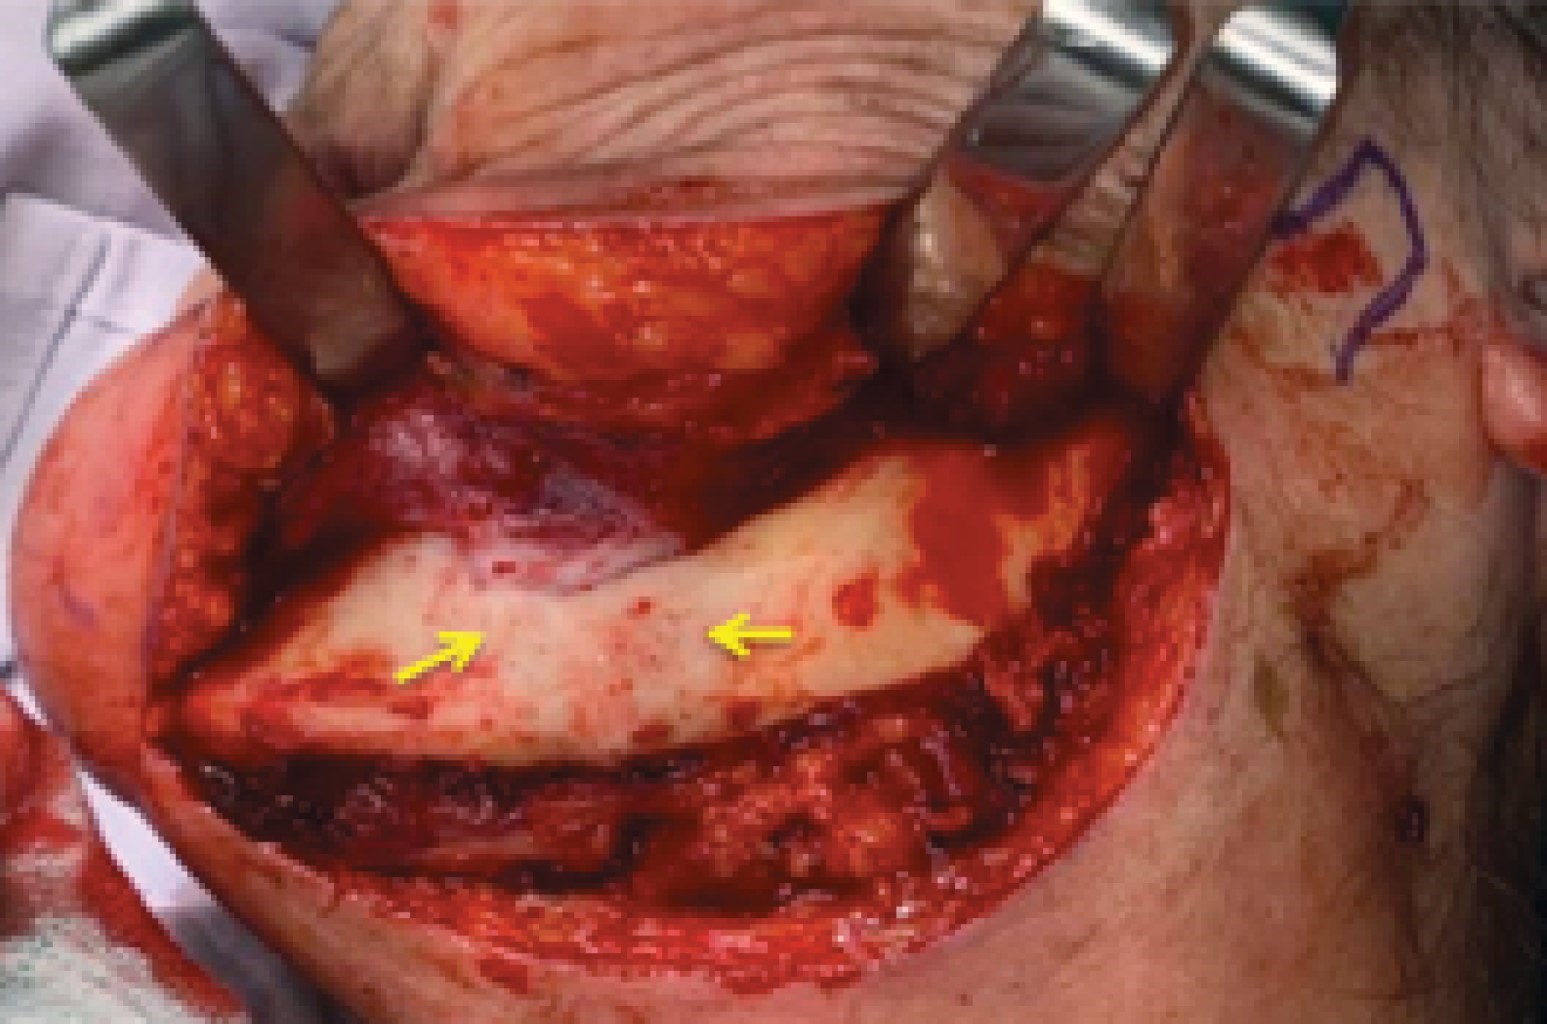

Posterior a un año de controles semanales y sin evidencia de ninguna mejoría posterior a las extracciones y manejo conservador, se decidió en conjunto con paciente y sus familiares manejo quirúrgico con resección mandibular izquierda, para lo que se solicitó TAC, reconstrucción 3D (Figuras 3 y 4), estereolitografía y todos los estudios de laboratorio pertinentes, así como valoración preoperatoria por cardiología, medicina interna y anestesiología, de igual manera el médico oncólogo tratante estuvo enterado y de acuerdo con el tratamiento propuesto.

Bajo anestesia general balanceada con intubación nasotraqueal, se realizó asepsia y antisepsia de la zona a intervenir. Se hizo abordaje extraoral tipo Risdon con extensión submental, se expuso en su totalidad hemimandíbula izquierda (Figura 5). Se colocó y fijó placa de reconstrucción 2.4 alto perfil, la cual fue predoblada con la estereolitografía y esterilizada. Se fijó placa con cinco tornillos 2.4 bicorticales en el segmento proximal y cuatro tornillos 2.4 bicorticales en el segmento distal, todos los tornillos utilizados fueron bloqueados. Diez días previos al procedimiento se inició manejo con doxiciclina 300 mg cada 12 horas según el protocolo descrito por Putke y colegas, de técnica de fluorescencia transoperatoria (Figura 6). Posterior a esto se realizó la resección en bloque con bordes óseos sanos según lo planeado tomográficamente y lo visto clínicamente con la técnica de fluorescencia (Figura 7). Se colocaron múltiples membranas de plasma rico en factores de crecimiento (Figura 8) y se realizó hemostasia, cierre por planos hacia el piso de la boca y de abordaje de Risdon y se colocó Penrose de abordaje cervical. Se dio por terminado el procedimiento quirúrgico, enviando pieza quirúrgica a patología (Figura 9). La paciente cursó con un postoperatorio adecuado (Figura 10).

Uno de los mayores problemas a los que nos enfrentamos al planear y realizar nuestros procedimientos quirúrgicos es la extensión de la enfermedad, debido a que con frecuencia lo que vemos clínicamente no es la extensión completa de la enfermedad, con base en esto, la literatura menciona algunos métodos coadyuvantes durante la planeación y el procedimiento quirúrgico. Se pueden utilizar tomografías pre y transoperatorias, centellografía ósea y la resonancia magnética pueden guiarnos durante nuestro tratamiento. Además, existe una técnica relativamente nueva: fluorescencia guiada de manera transoperatoria. Esta técnica reportada por Pautke y colaboradores se ha sugerido para diferenciar el hueso vital del hueso necrótico. En esta técnica se le administra al paciente tetraciclina 10 días previos a la intervención y durante el procedimiento quirúrgico se aplica luz fluorescente al área afectada y existe diferencia visual clara del hueso necrótico (el cual se observa azul-pálido) al hueso vital (brilloso y fluorescente).25 Además, también se ha reportado el uso de plasma rico en plaquetas (PRP) y la terapia de láser de baja intensidad como coadyuvantes en los procesos quirúrgicos. El PRP es una fuente autóloga de una gran variedad de factores de crecimiento que se ha utilizado en pacientes a los que se practicó desbridamiento o resecciones, ayudando de manera importante en la cicatrización de los tejidos blandos.26 Por su parte, se ha demostrado que el láser de baja intensidad regula el metabolismo, ayuda a la cicatrización de tejidos blandos, reduce el dolor y minimiza la contaminación por microorganismos, por estas razones se recomienda el uso simultáneo con cualquier terapia en OMIM, en especial, los tratamientos quirúrgicos en los que se elimina el hueso necrótico.27

Figura 4

Figura 5